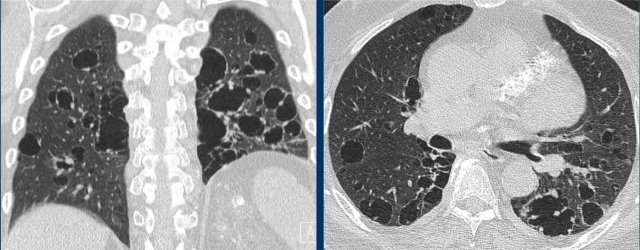

When there are multiple findings that look like cysts, one should distinguish a true cystic lung disease from other mimicking diseases as well (figure).

1. Multiple lung cysts with fine walls in a patient with advanced LCH. This is a true cystic lung disease.

2. Centrilobular emphysema, seen as black holes without a wall. Notice the central dot sign (arrow). Emphysema can be a real mimicker and we will discuss it in more detail later.

3. Honeycombing as a stack of thick walled cysts in the periphery of the lower lobes in patients with lung fibrosis.

4. Cystic bronchiectasis, seen as cystic tubes. This is usually not a problem as we can scroll through the images, but it can sometimes be challenging.